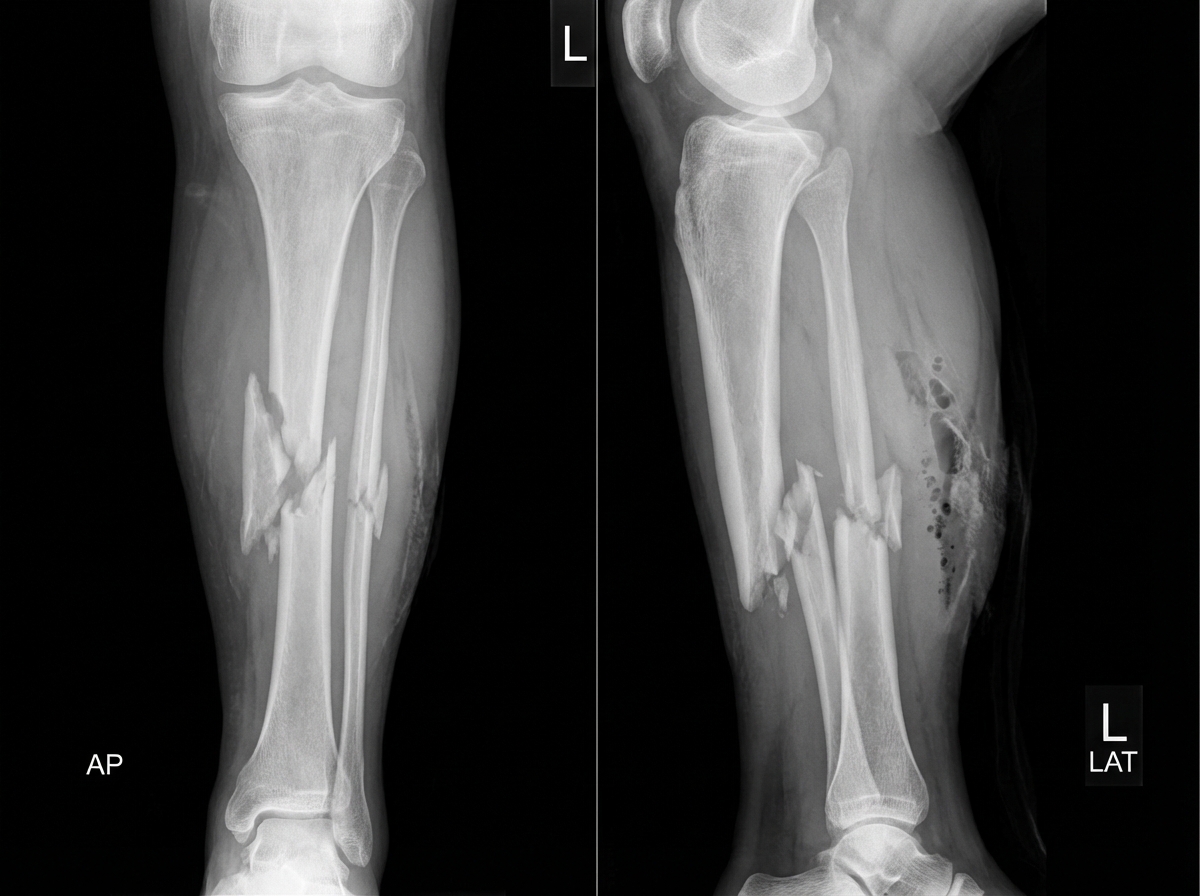

A 22-year-old man is brought to the emergency department following a rugby injury. Which of the following statements is false regarding the fracture shown?

Explanation: ***Closed fracture*** - This statement is **FALSE** - the fracture is actually an **open (compound) fracture** with visible bone fragments through the skin. - Open fractures require immediate **surgical debridement** and **antibiotic prophylaxis** to prevent infection and are classified using the **Gustilo-Anderson system**. *Comminuted fracture of the tibia* - This statement is **TRUE** - the fracture shows **multiple bone fragments** characteristic of a comminuted pattern. - Common in **high-energy trauma** like sports injuries, requiring complex surgical fixation with **intramedullary nailing** or **external fixation**. *Does not involve the articular surface* - This statement is **TRUE** - the fracture is located in the **mid-shaft (diaphysis)** of the tibia, sparing the joint surfaces. - **Diaphyseal fractures** have better healing potential compared to **intra-articular fractures** which can lead to post-traumatic arthritis. *Posteriorly displaced fracture* - This statement is **TRUE** - the **distal fragment** is displaced posteriorly relative to the proximal fragment. - Posterior displacement can compromise the **popliteal artery** and **posterior tibial nerve**, requiring vascular and neurological assessment.